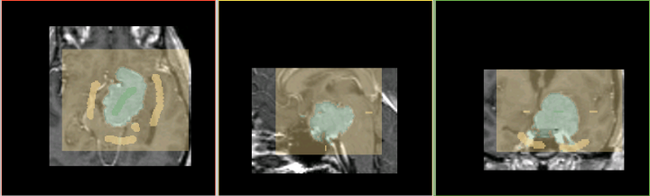

After the segmentation, the user can edit the segmentation by providing additional gestures in the image as illustrated in the figure below.

Additional edits added to the existing segmentation

Final segmentation

The segmentation resulting from the user's edit is also shown.